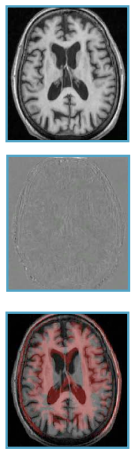

图像相似度的度量-示例

- 用于相同强度 +高斯噪声的差平方和(SSD)Sum of squared differences

- 仿射关系的标准化互相关(NCC) Normalised Cross-correlation:光照差异小,对比度变化小;局部化版本(LNCC)提供了良好的通用性

- 联合熵,用于强度之间的非参数统计关系的联合图像直方图中的散度和(标准化)相互信息:多模态配准